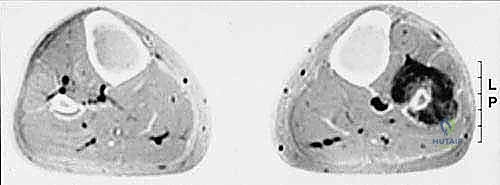

- التصوير بالرنين المغناطيسي (MRI): المعيار الذهبي. يوضح بدقة متناهية امتداد الورم داخل نخاع العظم، وحجم الكتلة في الأنسجة الرخوة المحيطة، وعلاقة الورم بالأعصاب والأوعية الدموية.

- التصوير المقطعي المحوسب (CT Scan): ممتاز لتقييم التفاصيل الدقيقة للقشرة العظمية واكتشاف أي تكلسات داخل الورم.